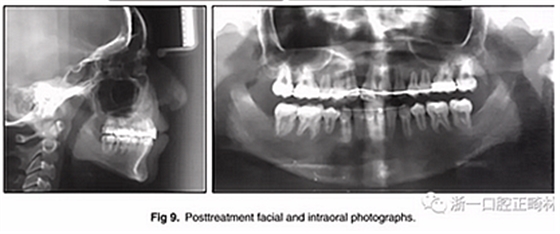

兩年半后,在上下牙弓上均實(shí)現(xiàn)了間隙關(guān)閉,并且使用0.017×0.025英寸的不銹鋼弓絲進(jìn)行咬合精細(xì)調(diào)整(圖8)。去除托槽后,上下頜采用舌側(cè)弓進(jìn)行保持(圖9)。

總體治療目標(biāo)已經(jīng)實(shí)現(xiàn)。病人的笑容和輪廓有所改善。咬合關(guān)系為I類磨牙關(guān)系,牙列整齊,牙尖交錯(cuò)關(guān)系良好。反合和中線偏移得以矯正,并實(shí)現(xiàn)了正常的覆蓋和覆合。上下牙弓的擁擠問題完全解決,并且完成后全景片顯示良好的牙根傾斜度。疊加顯示良好的縱向和垂直控制(ANB,3.5°; SN / GoMe,42.5°)和矯正上下頜前牙傾斜度(1 / SN,96°; IMPA,87°)(圖10 ; 表)。

在治療結(jié)束時(shí)沒有觀察到顳下頜關(guān)節(jié)紊亂的體征或癥狀,但發(fā)現(xiàn)了輕微的牙根吸收以及裂隙區(qū)域的骨頭輕度丟失。

治療持續(xù)3年,患者始終保持積極和合作??谇恍l(wèi)生很好?;颊吆退母改付紝?duì)結(jié)果感到滿意。